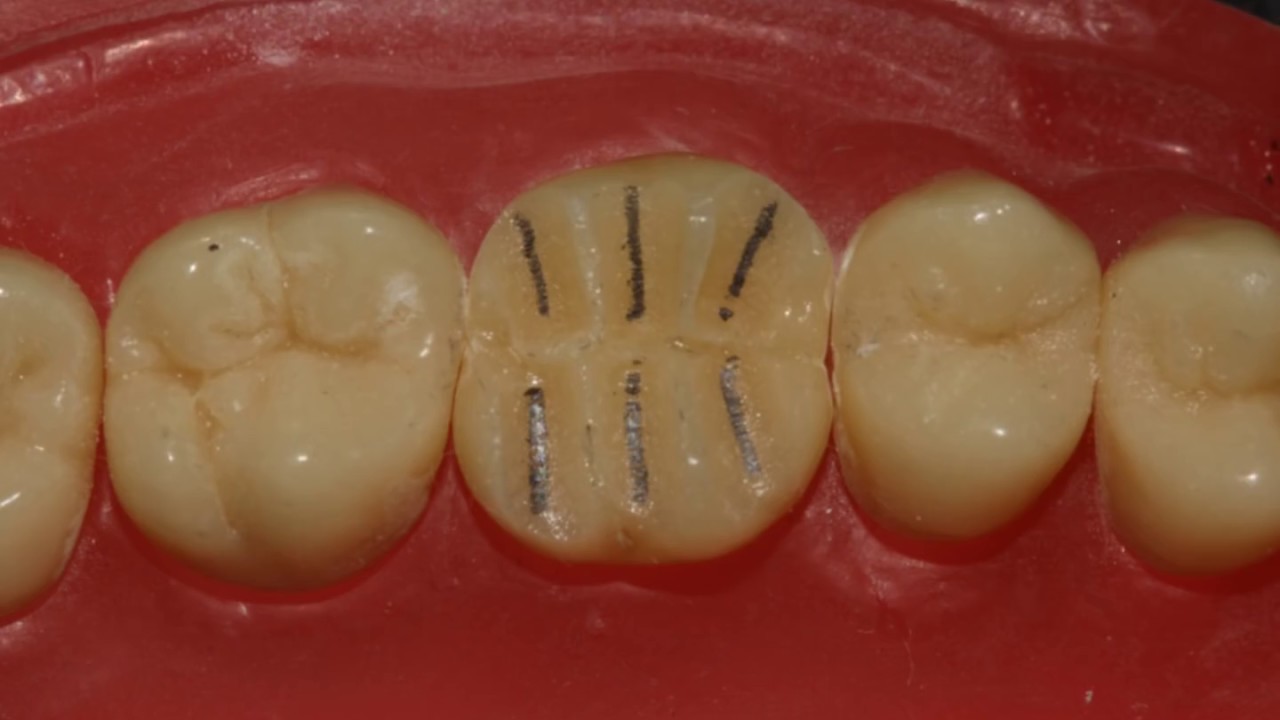

MOD Ceramic Onlay Dental Preparation Video Onlay Ceramica Onlay longevity can be enhanced if the preparation allows for at least 2 mm occlusal ceramic thickness and incorporates additional. The most common pattern of failure is fracture of the ceramic material. Porcelain onlays blend seamlessly with the natural tooth color, making them virtually undetectable. Ceramic onlay appears to be a reliable option to restore posterior teeth. It is a. Onlay Ceramica.

Preparación para la fijación de la corona cerámica Onlay sobre el Onlay Ceramica Onlay longevity can be enhanced if the preparation allows for at least 2 mm occlusal ceramic thickness and incorporates additional. Porcelain onlays blend seamlessly with the natural tooth color, making them virtually undetectable. A total of 21 studies met the selection criteria and were deemed suitable for. This case report discusses the preparation of a functional and aesthetic ceramic onlay. Onlay Ceramica.